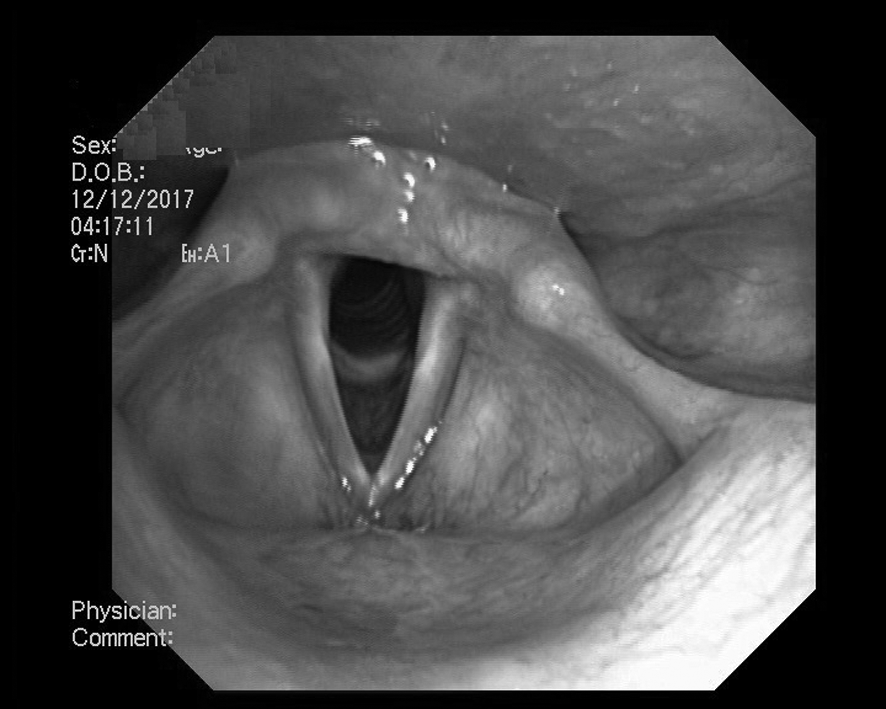

По данным видеоэндоскопического исследования от 12.12.17 перед началом курса голосовой реабилитации (рис. 1), слизистая гортани розовая, голосовая щель свободная, широкая, голосовые складки ровные, слизистая бледно-розовая, блестящая. Отмечается латеральное положение левой голосовой складки. Подскладочный отдел свободен (состояние гортани при дыхании).

Рис. 1. Парез гортани слева. Положение голосовых складок при дыхании. До начала лечения.